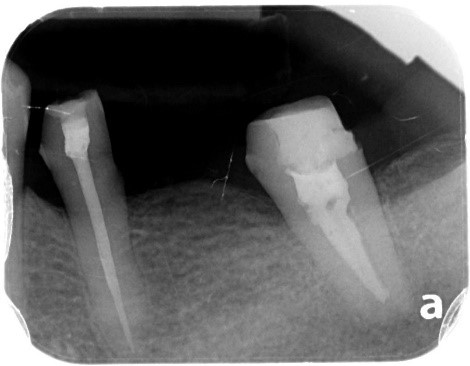

案例:蓄意再植

原先病人做牙橋的大臼齒因為牙根發炎,疼痛難耐,前來做根管治療,但因為大臼齒牙根末端神經較複雜、且有張口困難的問題,因此更增加了做根管治療的困難度,在經醫師評估後,建議做蓄意再植手術。

將牙齒拔出後,在口外做根管治療、並且切除牙根末端神經較複雜處。

醫師在口外對牙齒完成治療後,再將牙齒植入同一位置

治療前:蛀牙嚴重、牙根發炎。

治療前X光片。

治療中:牙齒在口外治療完種回去,並用鐵線固定,等待傷口復原.

治療中:將牙齒修型、將鐵線拆除